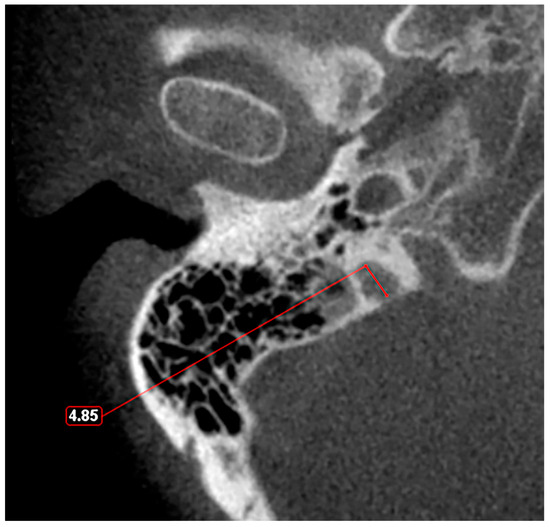

3. Diverticula

The “Condylar Jugular Diverticulum”: True or False?